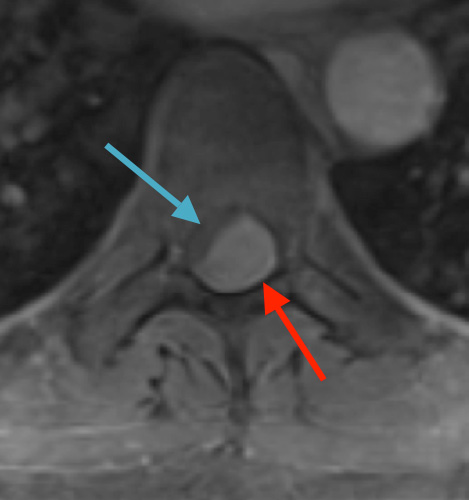

Preoperative MRI T1w demonstrating a large enhancing tumor (red arrow) causing severe cord compression and displacement (blue arrow)

Postoperative MRI T1w demonstrating interval resection with cord re-expansion (blue arrow)